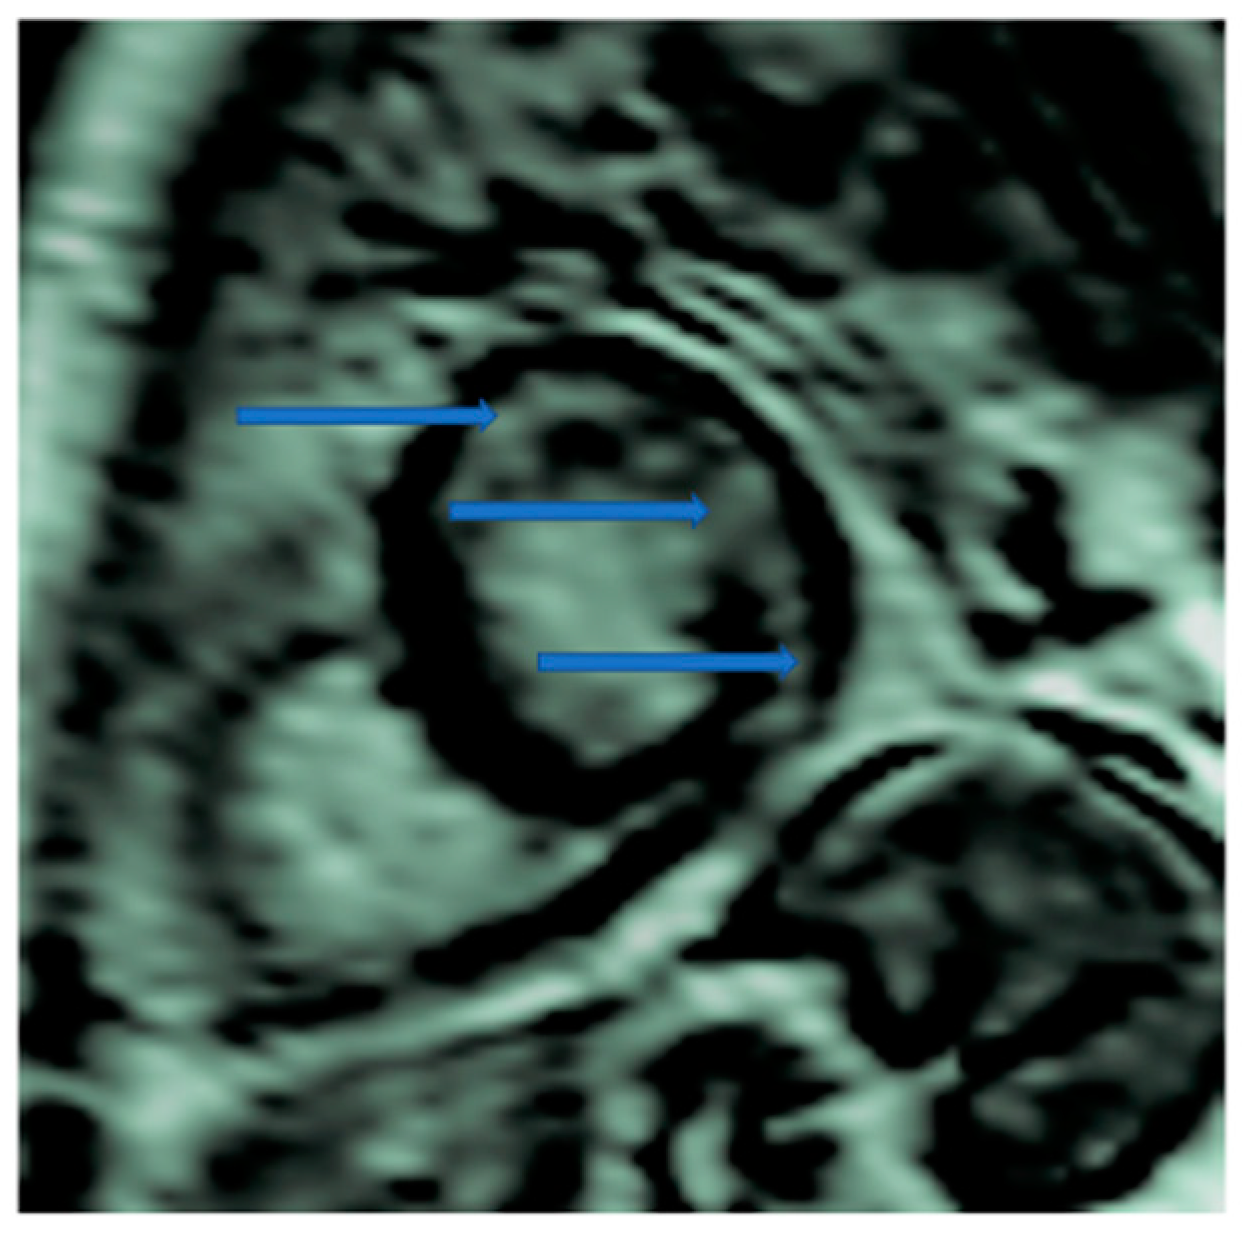

4.5. Myocardial Edema-Fibrosis Assessment